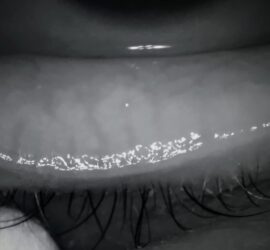

Dry eye treatments available Meibomian gland expression therapy Micro-blepharo Exfoliation (Blephex) Punctum plugs Intense Regulated Pulsed Light IRPL If you have been suffering ...

Professional Eyelid Cleaning | BlephEx™

What is BlephEx™ treatment? Professional eye lid cleaning gives you a head start in your lid hygiene routine. We all brush our teeth twice a day but we still see the dentist to have a super ...

IPL for Dry Eyes

Dedicated to the treatment of eye dryness in its evaporative form resulting from meibomian gland dysfunction. E-Eye IRPL technology is non-invasive, painless and does not harm the eye. IPL (Intense ...

Meibomian Gland Expression at IQ Optometry

Meibomian Gland Expression

Meibomian gland expression therapy is useful when you have dry eye due to blocked meibomian glands and you have found self-care options less effective. This therapy involves the mechanical, therapeutic ...